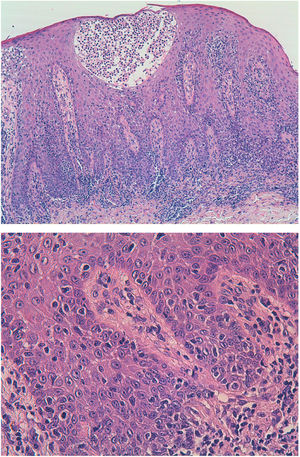

Histological image showing lymphocytic infiltrate throughout the thickness of the epithelium, with a parabasal distribution, marked epidermotropism, and the presence of Pautrier microabscesses. These lymphocytes are also observed in the superficial dermis. The lymphocytes are atypical, with angular, cerebriform, cleft nuclei.

A 42-year-old man with no past history of interest was seen for asymptomatic lesions that had appeared 2 years earlier. These polymorphic and evanescent lesions consisted of psoriasiform and circular eczematous elements, some with circinate morphology (Fig. 1), and had been treated with multiple topical and oral treatments for the clinical diagnosis of dermatomycosis, eczema, and psoriasis. Fever, weight loss, profuse sweating, and other systemic clinical signs were absent. An initial biopsy revealed superficial lymphohistiocytic dermatitis with a psoriasiform pattern. A second biopsy showed atypical lymphocytic infiltrate (with angular, cerebriform, cleft nuclei) throughout the thickness of the epithelium, with a parabasal distribution, marked epidermotropism, and the presence of Pautrier microabscesses. These lymphocytes were also evident in the superficial dermis. The immunophenotype was positive for T-cell markers (cytoplasmic CD3 and CD2), with partial loss of CD5, and negative for CD4, CD8, CD7, and CD45RO. Analyses revealed negative T cell receptor (TCR) α and TCRβ gene rearrangement, and negative staining for CD30, PD1, and CD56. Cytotoxic markers (granzyme B, perforin, and TIA1) were detected (Figs. 2 and 3), and in situ hybridization for Epstein-Barr virus early transcripts (EBERs) was negative.